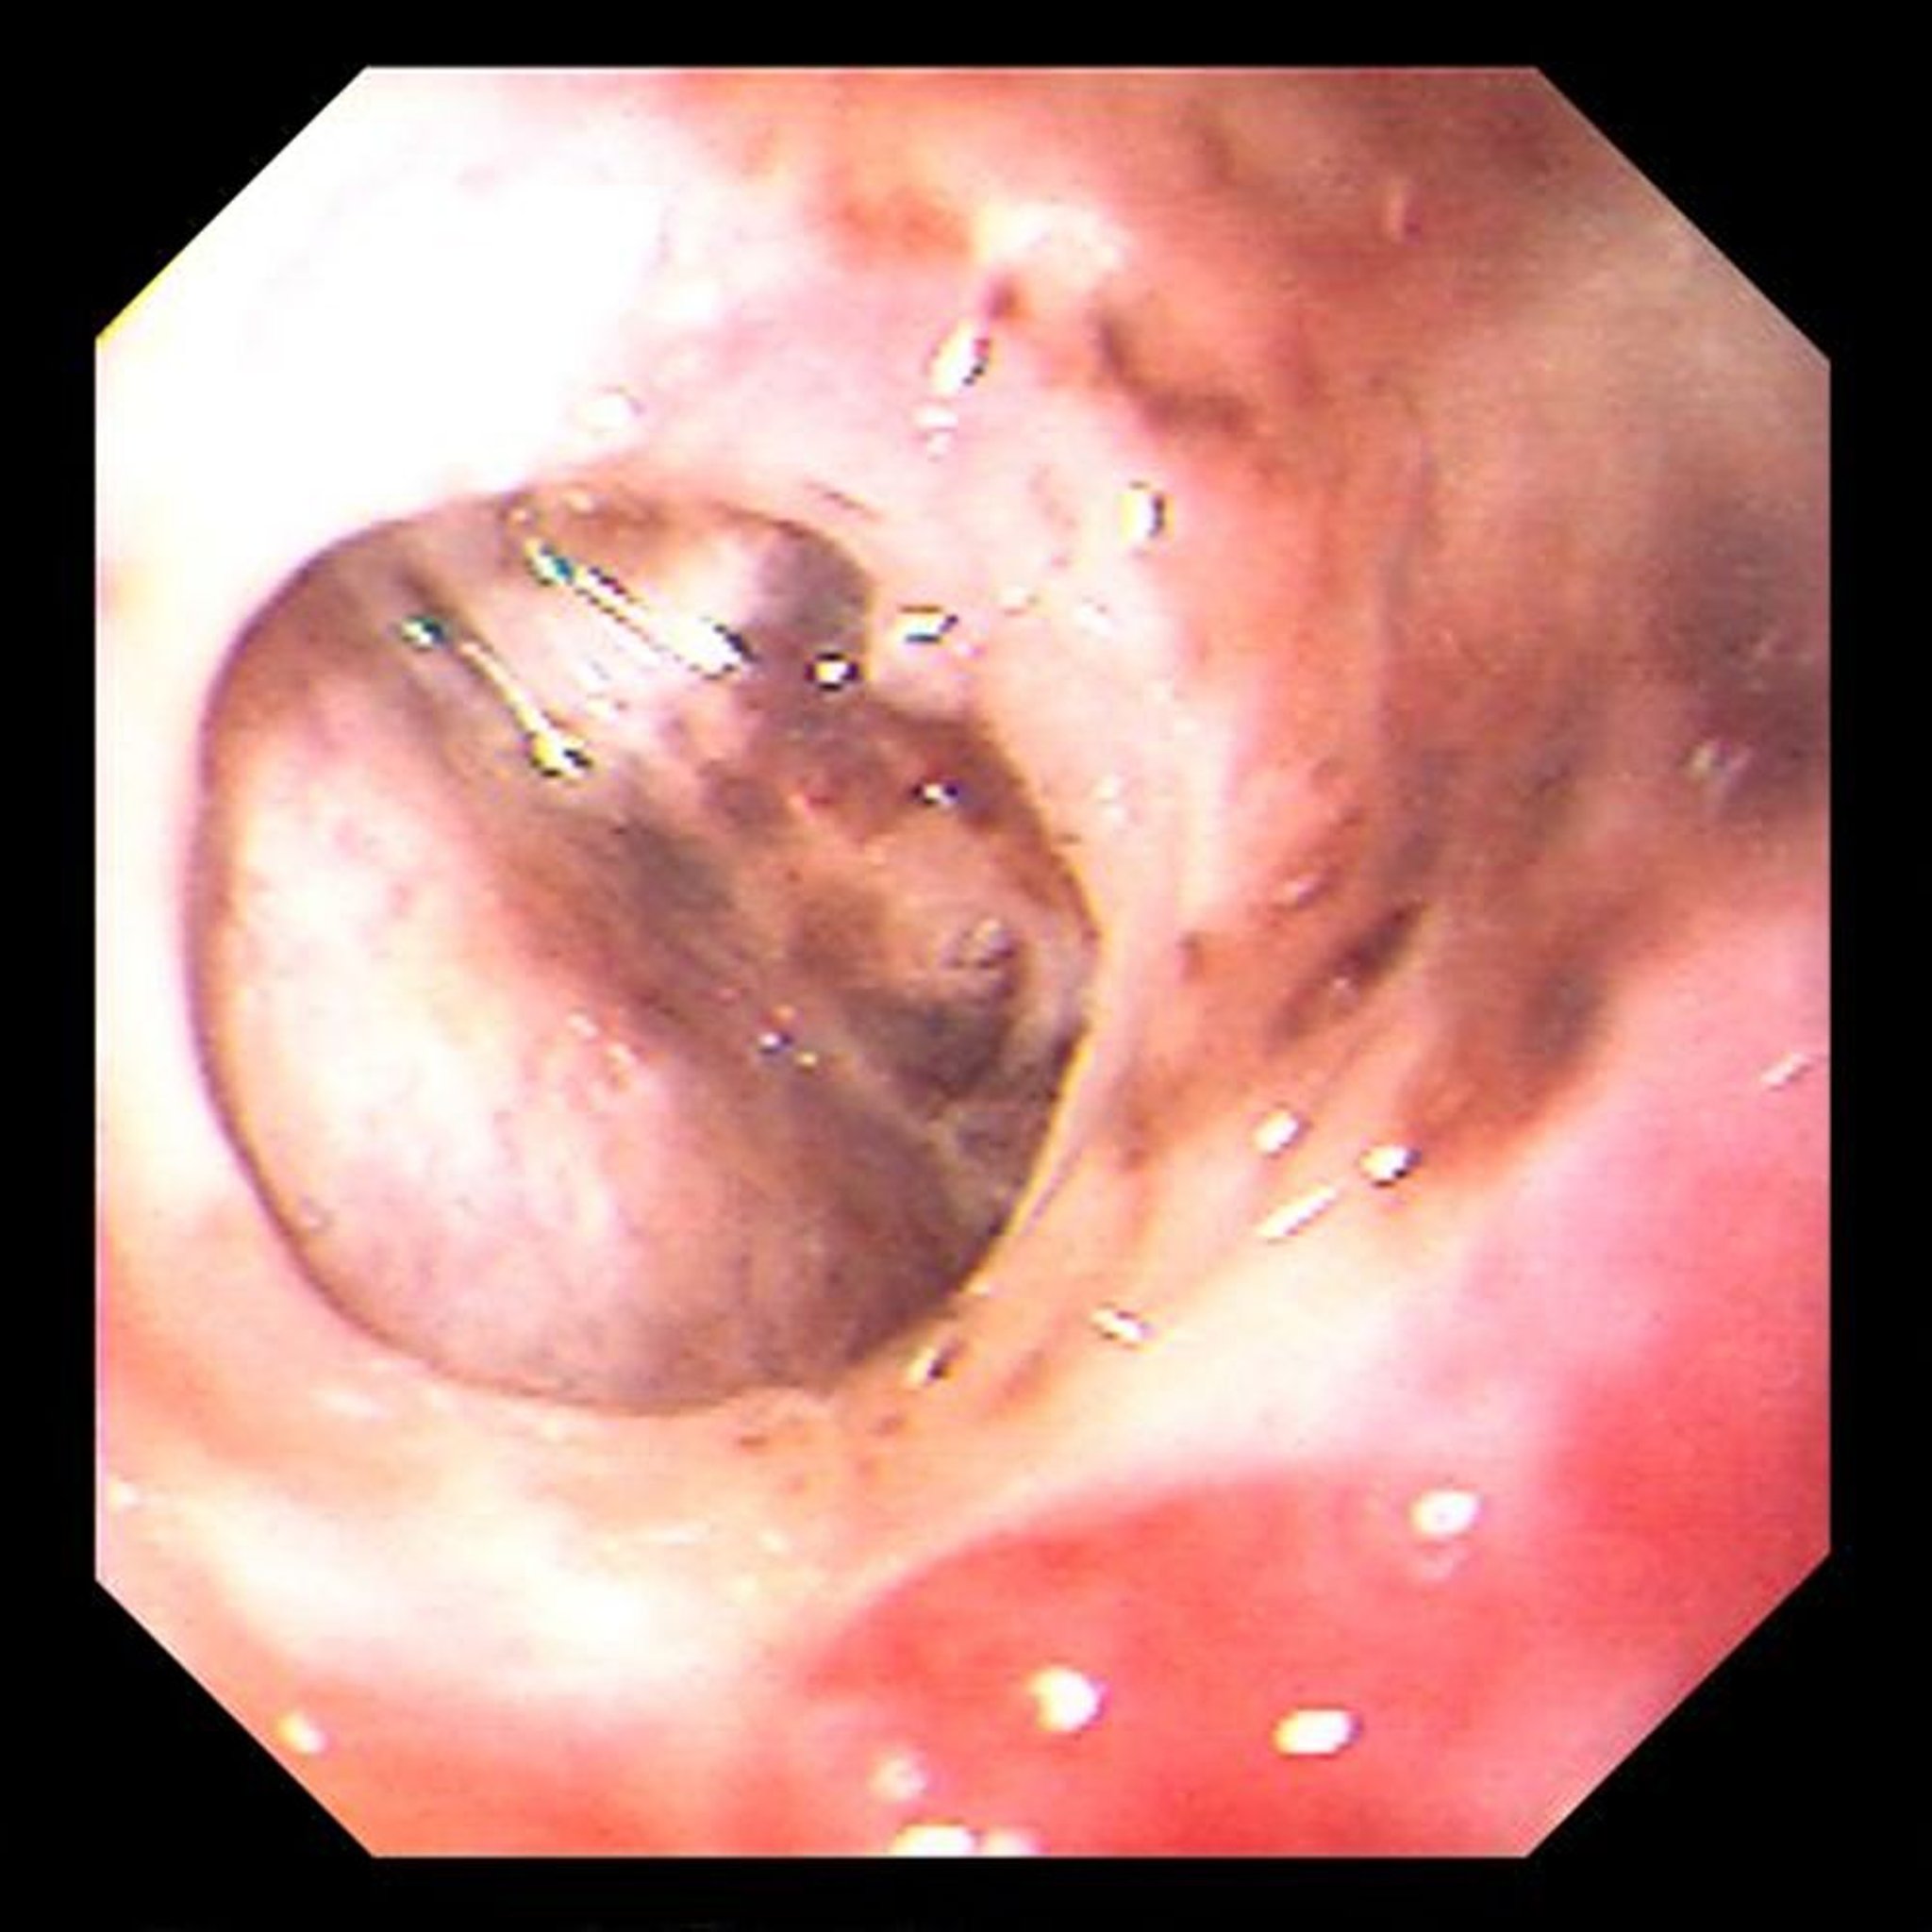

Perfuração por úlcera gástrica

Essa imagem mostra uma úlcera gástrica perfurada crônica e confinada, através da qual o fígado pode ser visto.

Image provided by David M. Martin, MD.